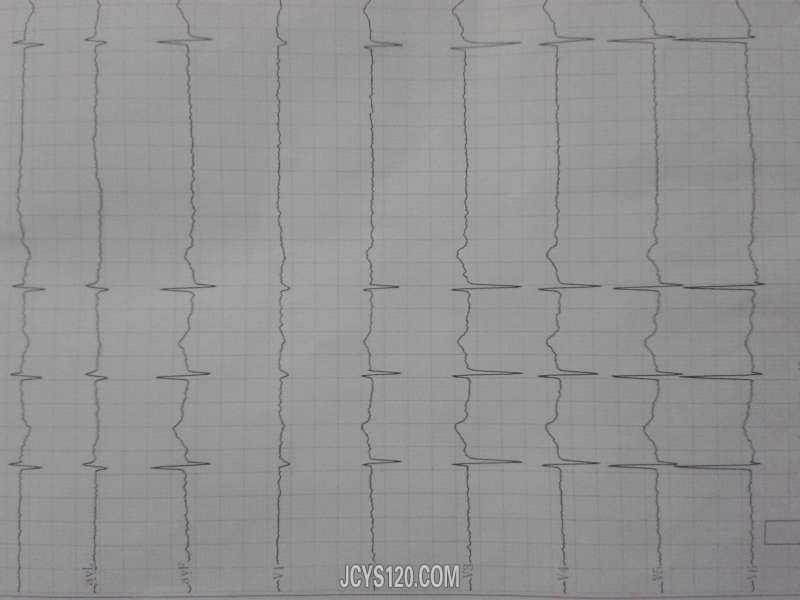

• 心慌胸闷十几个小时。 attach_img agree

• 心常平 2013-12-3

• 一般资料:患者男,年龄42岁,已婚·,职业:洗车工。 主诉:心慌胸闷十几个小时 现病史:患者于昨晚无诱因出现心慌胸闷,无憋气,无头晕,出汗等表现。自己摸脉搏感觉心律不齐,自行口服救心丸5粒(舌下)十几分 ...  阅读全文>